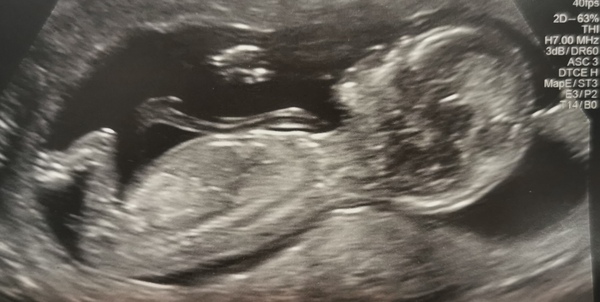

All well today guys, one happy wriggly baby. Took a while to get the measurements as baby was being awkward, I was so glad to see baby I'd have happily led there for hours waiting 😁 EDD 30th April, bang on 13 weeks today!

@Busybee143 that’s brilliant - and such a clear picture. Bring on April Smile

What a beauty, that’s such good news @Busybee143 you give me hope!

Congrats @Busybee143 I'm putting my money on a boy! Lol